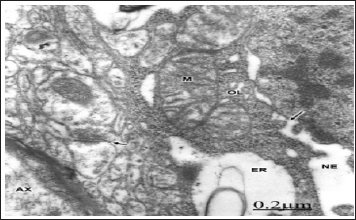

The swollen and clear astrocytes display marked degenerative changes induced by brain edema in comparison with those exhibited by neuronal cells. Areas of focal necrosis and fragmented limiting plasma membrane, over-distended rough endoplasmic reticulum cisterns with extended degranulated areas, and vacuoles of smooth endoplasmic reticulum with necrotic limiting membrane are found [80-82] (Figure 8). Oligodendroglial cells show also marked edematous changes featured by lacunar enlargement of rough endoplasmic reticulum and nuclear envelope, detachment of membrane bound ribosomes, swollen mitochondria associated to rough endoplasmic reticulum, and discontinuous plasma membrane [83,84]. (Figure 9). The endoplasmic reticulum is a subcellular compartment playing a fundamental role in the folding and processing of newly synthesized membranes and secretory processes, reactions which are strictly calcium/dependent. Severe disruption of neuronal Ca2+ homeostasis leading to a lethal Ca2+ overload as occurs in brain ischemia, can initiate a cascade of destructive processes which lead to the death of neurons during cerebral ischemia [85-86]. As stated above endoplasmic reticulum function is disturbed in many acute and chronic diseases of the brain, such as Parkinson's and Alzheimer's diseases [87]. Therefore, endoplasmic reticulum dysfunction is basically important to elucidate the pathogenetic mechanisms of neurodegeneration.

Figure 9: Brain trauma. Hydropic oligodendrocyte (OL) showing over-distended perinuclear (PN) and endoplasmic reticulum (ER) cisterns, disassembly of nuclear envelope (NE), and nuclear pores (long arrow). Note the swollen mitochondria (M) associated to rough endoplasmic reticulum. The neighboring neuropile exhibits degenerated axodendritic synapse (short arrow) and myelinated axon (AX). X 60.000.